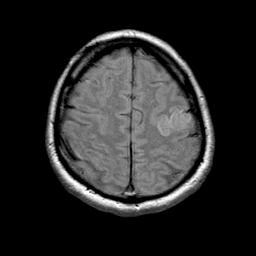

MR Study #1 -- Slice #19

[Home][Help][Clinical][Tour 1] Slice 19